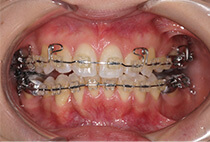

治療後